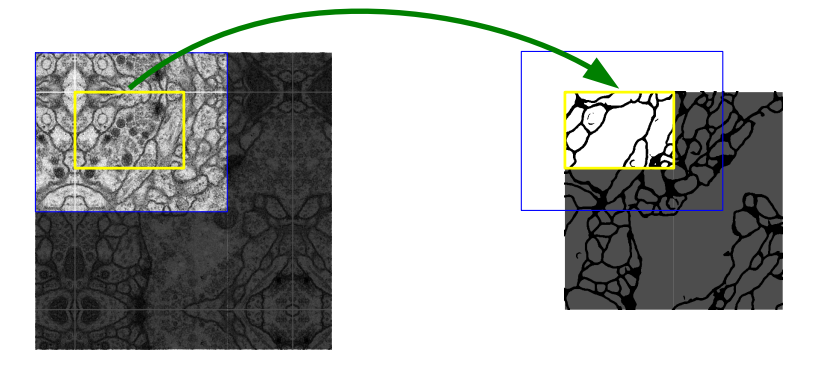

3.1 数据集介绍

数据来自于 ISBI 挑战的数据集。该数据集包含30张训练图、30张对应的标签。30张测试图片。数据是来自果蝇一龄幼虫腹神经索 (VNC) 的串行部分透射电子显微镜 (ssTEM)的图像,其分辨率为4x4x50 nm /像素。

输入原始图像:

模型输出图像: